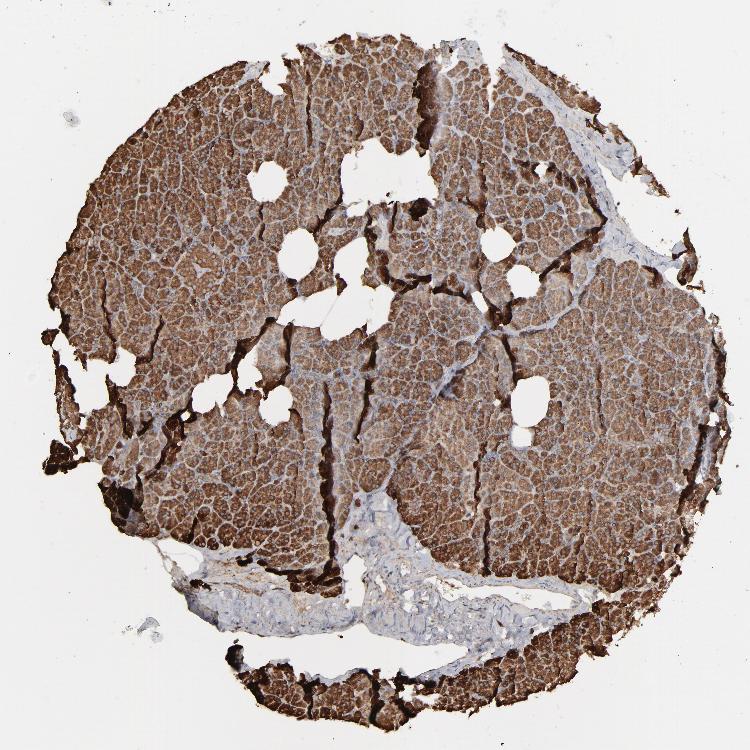

PANCREAS - Antibody stainingi

Antibody staining in the annotated cell types in the current human tissue is reported as not detected, low, medium, or high, based on conventional immunohistochemistry profiling in selected tissues. This score is based on the combination of the staining intensity and fraction of stained cells.

Each image is clickable and will lead to virtual microscopy that enables deeper exploration of all samples and also displays staining intensity scores, fraction scores and subcellular localization as well as patient and tissue information for each sample.

Antibody HPA008467Antibody HPA041113Antibody CAB002169Antibody CAB076057

Exocrine glandular cells HighMediumHighMedium

Pancreatic endocrine cells -LowHighLow